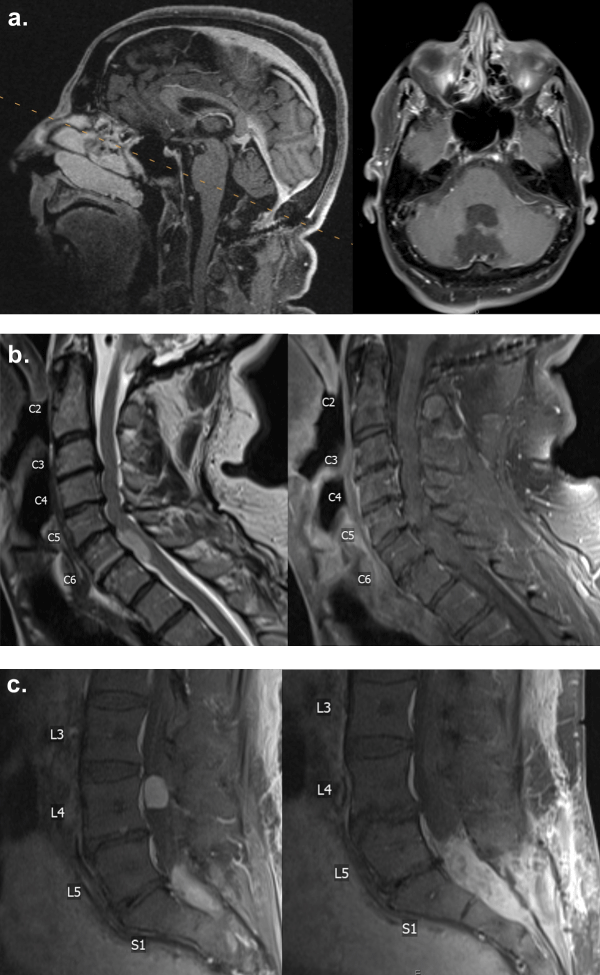

At the age of 56, the patient presented with radicular pain radiating from the left buttock down the left lateral thigh, as well as numbness and tingling in the left posterior thigh, after a fall three months prior. The physical examination demonstrated full strength in bilateral upper and lower extremities. Reflexes were unremarkable. A magnetic resonance imaging (MRI) with and without gadolinium contrast of the entire neuraxis, including brain, cervical, thoracic, and lumbar spines, as well as a computed tomography (CT) with contrast of the chest, abdomen, and pelvis, was ordered to evaluate for metastatic disease. MRI of the brain demonstrated a questionable enhancement in the posterior fossa resection bed (Figure 1a). MRI of the cervical and lumbar spines demonstrated a non-enhancing 1.7 cm lesion anterior to the spinal cord at the C6-7 levels, a 1.6 cm enhancing lesion eccentric to the left in the thecal sac at the L4 level, and a 5.6 cm enhancing lesion in the thecal sac of the sacrum (Figure 1b and Figure 1c). These three intradural extramedullary lesions were suggestive of drop metastases from the patient’s prior ependymoma.

Figure 1: MRI with gadolinium contrast demonstrating. (a): The posterior fossa; (b): A non-enhancing lesion at the C6-7 level; (c): An enhancing lesion at the L4 level and an enhancing lesion in the sacral thecal sac. View Figure 1